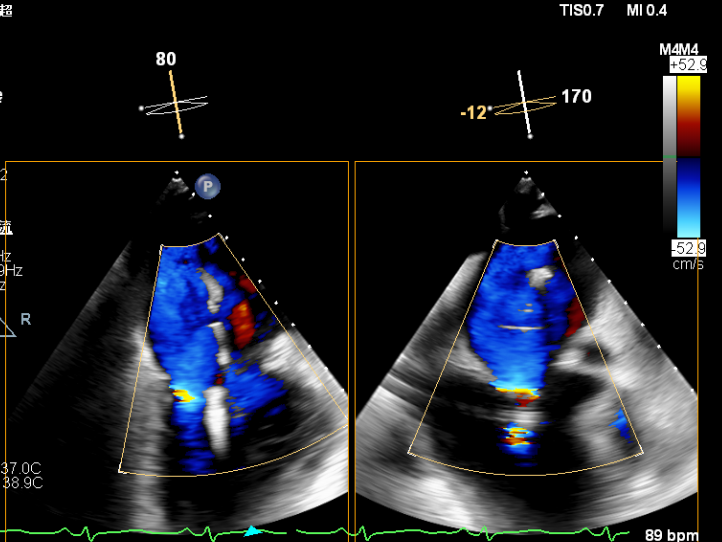

术后即刻超声提示二尖瓣反流下降至微量,二尖瓣平均跨瓣压2mmHg,多切面证实夹合组织充分,左上肺静脉多普勒波形由反向恢复正常。

2.X-plane切面调整瓣膜夹的位置:主要定位PISIA最明显的A2/P2区,分别二尖瓣交界联合切面和 LVOT切面调整夹子轴向,同时在3D切面上观察夹子方位和区域,瓣膜夹位置良好,轴向和方位均理想后,捕获A2/P2偏1区处的前后瓣叶,逐渐关闭瓣膜夹,TEE显示二尖瓣反流明显减轻至微量,3D视角显示组织桥连续完整,瓣叶抓捕稳定。彩色血流提示微量的瓣膜反流,测量平均跨瓣压差3mmHg,复查左上肺静脉血流频谱恢复正向,手术效果理想,逐步释放瓣膜夹系统撤出体外。